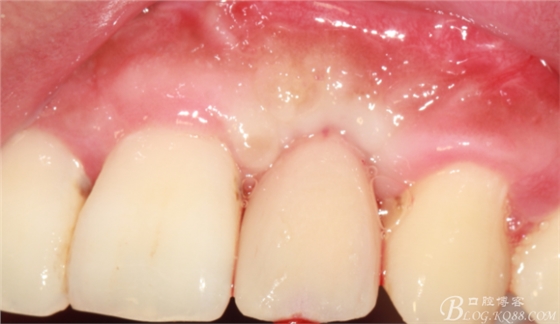

事實(shí)證明,我的做法沒有錯(cuò)誤,一個(gè)月后,軟組織健康愈合。鄰牙軟組織沒有退縮。

4個(gè)月后,唇側(cè)豐滿度尚可,與鄰牙之間齦乳頭完整。